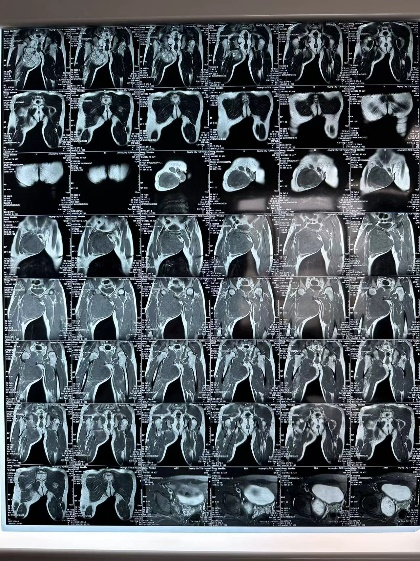

图片 8.png图片 10.png图片 9.png

3d建模

患者的肿瘤累及右侧耻骨上下支(Enneking Ⅲ区),预计截骨范围为耻骨联合到耻骨上支、耻骨下支到坐骨体内侧。由于肿物体积巨大,无论采用髂股入路还是髂腹股沟入路,单纯前路手术很难暴露坐骨及髋臼后柱结构,而在前路强行提拉推压肿物则会增加肿瘤破裂的风险。通过延伸Gibson入路,可以清晰的显露坐骨支,完整地显露截骨边界,降低肿瘤破裂及血管损伤的风险。由于该部分区域为非负重区,因此,无需进行骨盆环重建,但需要注意盆壁的修补,预防盆腔器官受重力作用下垂相关并发症。